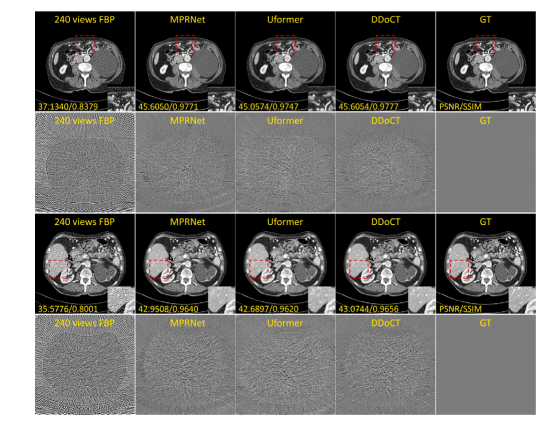

Fig. 5. Comparison of visual (together with quantitative results of PSNR and SSIM)and difference images of the Mayo testing dataset. The set range of the display windowis a window level of 40 HU and a window width of 400 HU (i.e., a range from −160HU to 240 HU). As for the difference images of the latter, the set range of the displaywindow is a window level of 0 HU and a window width of 200 HU (i.e., a range from−100 HU to 100 HU).

图5. Mayo测试数据集中视觉效果(以及PSNR和SSIM的定量结果)和差异图像的对比。显示窗口的设置范围为窗位40 HU,窗宽400 HU(即范围为−160 HU到240 HU)。对于后者的差异图像,显示窗口的设置范围为窗位0 HU,窗宽200 HU(即范围为−100 HU到100 HU)。